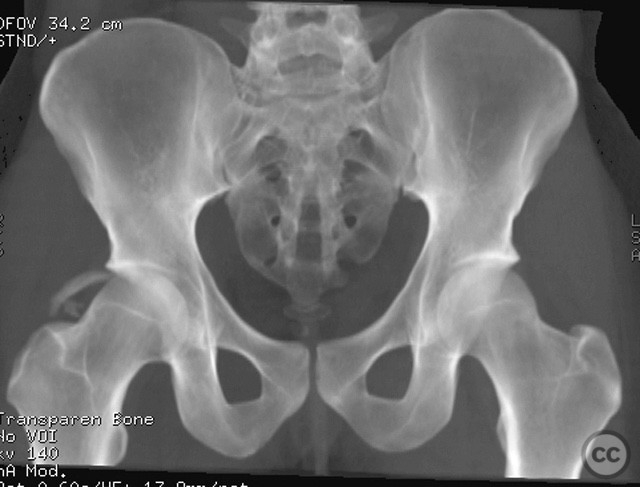

Follow up:   At one year post-injury, radiographs demonstrated maintained reduction and implant integrity. The patient returned to competitive basketball four months after surgery without restriction.